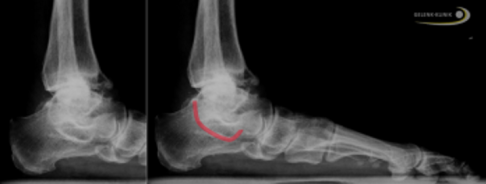

Bei Verdacht auf eine Coalitio talocalcanearis sucht der Fußspezialist nach dem sogenannten “C-Zeichen”: Die knöcherne Verbindung zwischen Sprungbein und Fersenbein erscheint im Röntgenbild wie ein auf dem Rücken liegendes "C".

Röntgenaufnahme einer Coalitio talocalcanearis: Die rote Linie markiert die Verknöcherung zwischen Talus und Calcaneus und bildet ein liegendes "C." © Gelenk-Klinik